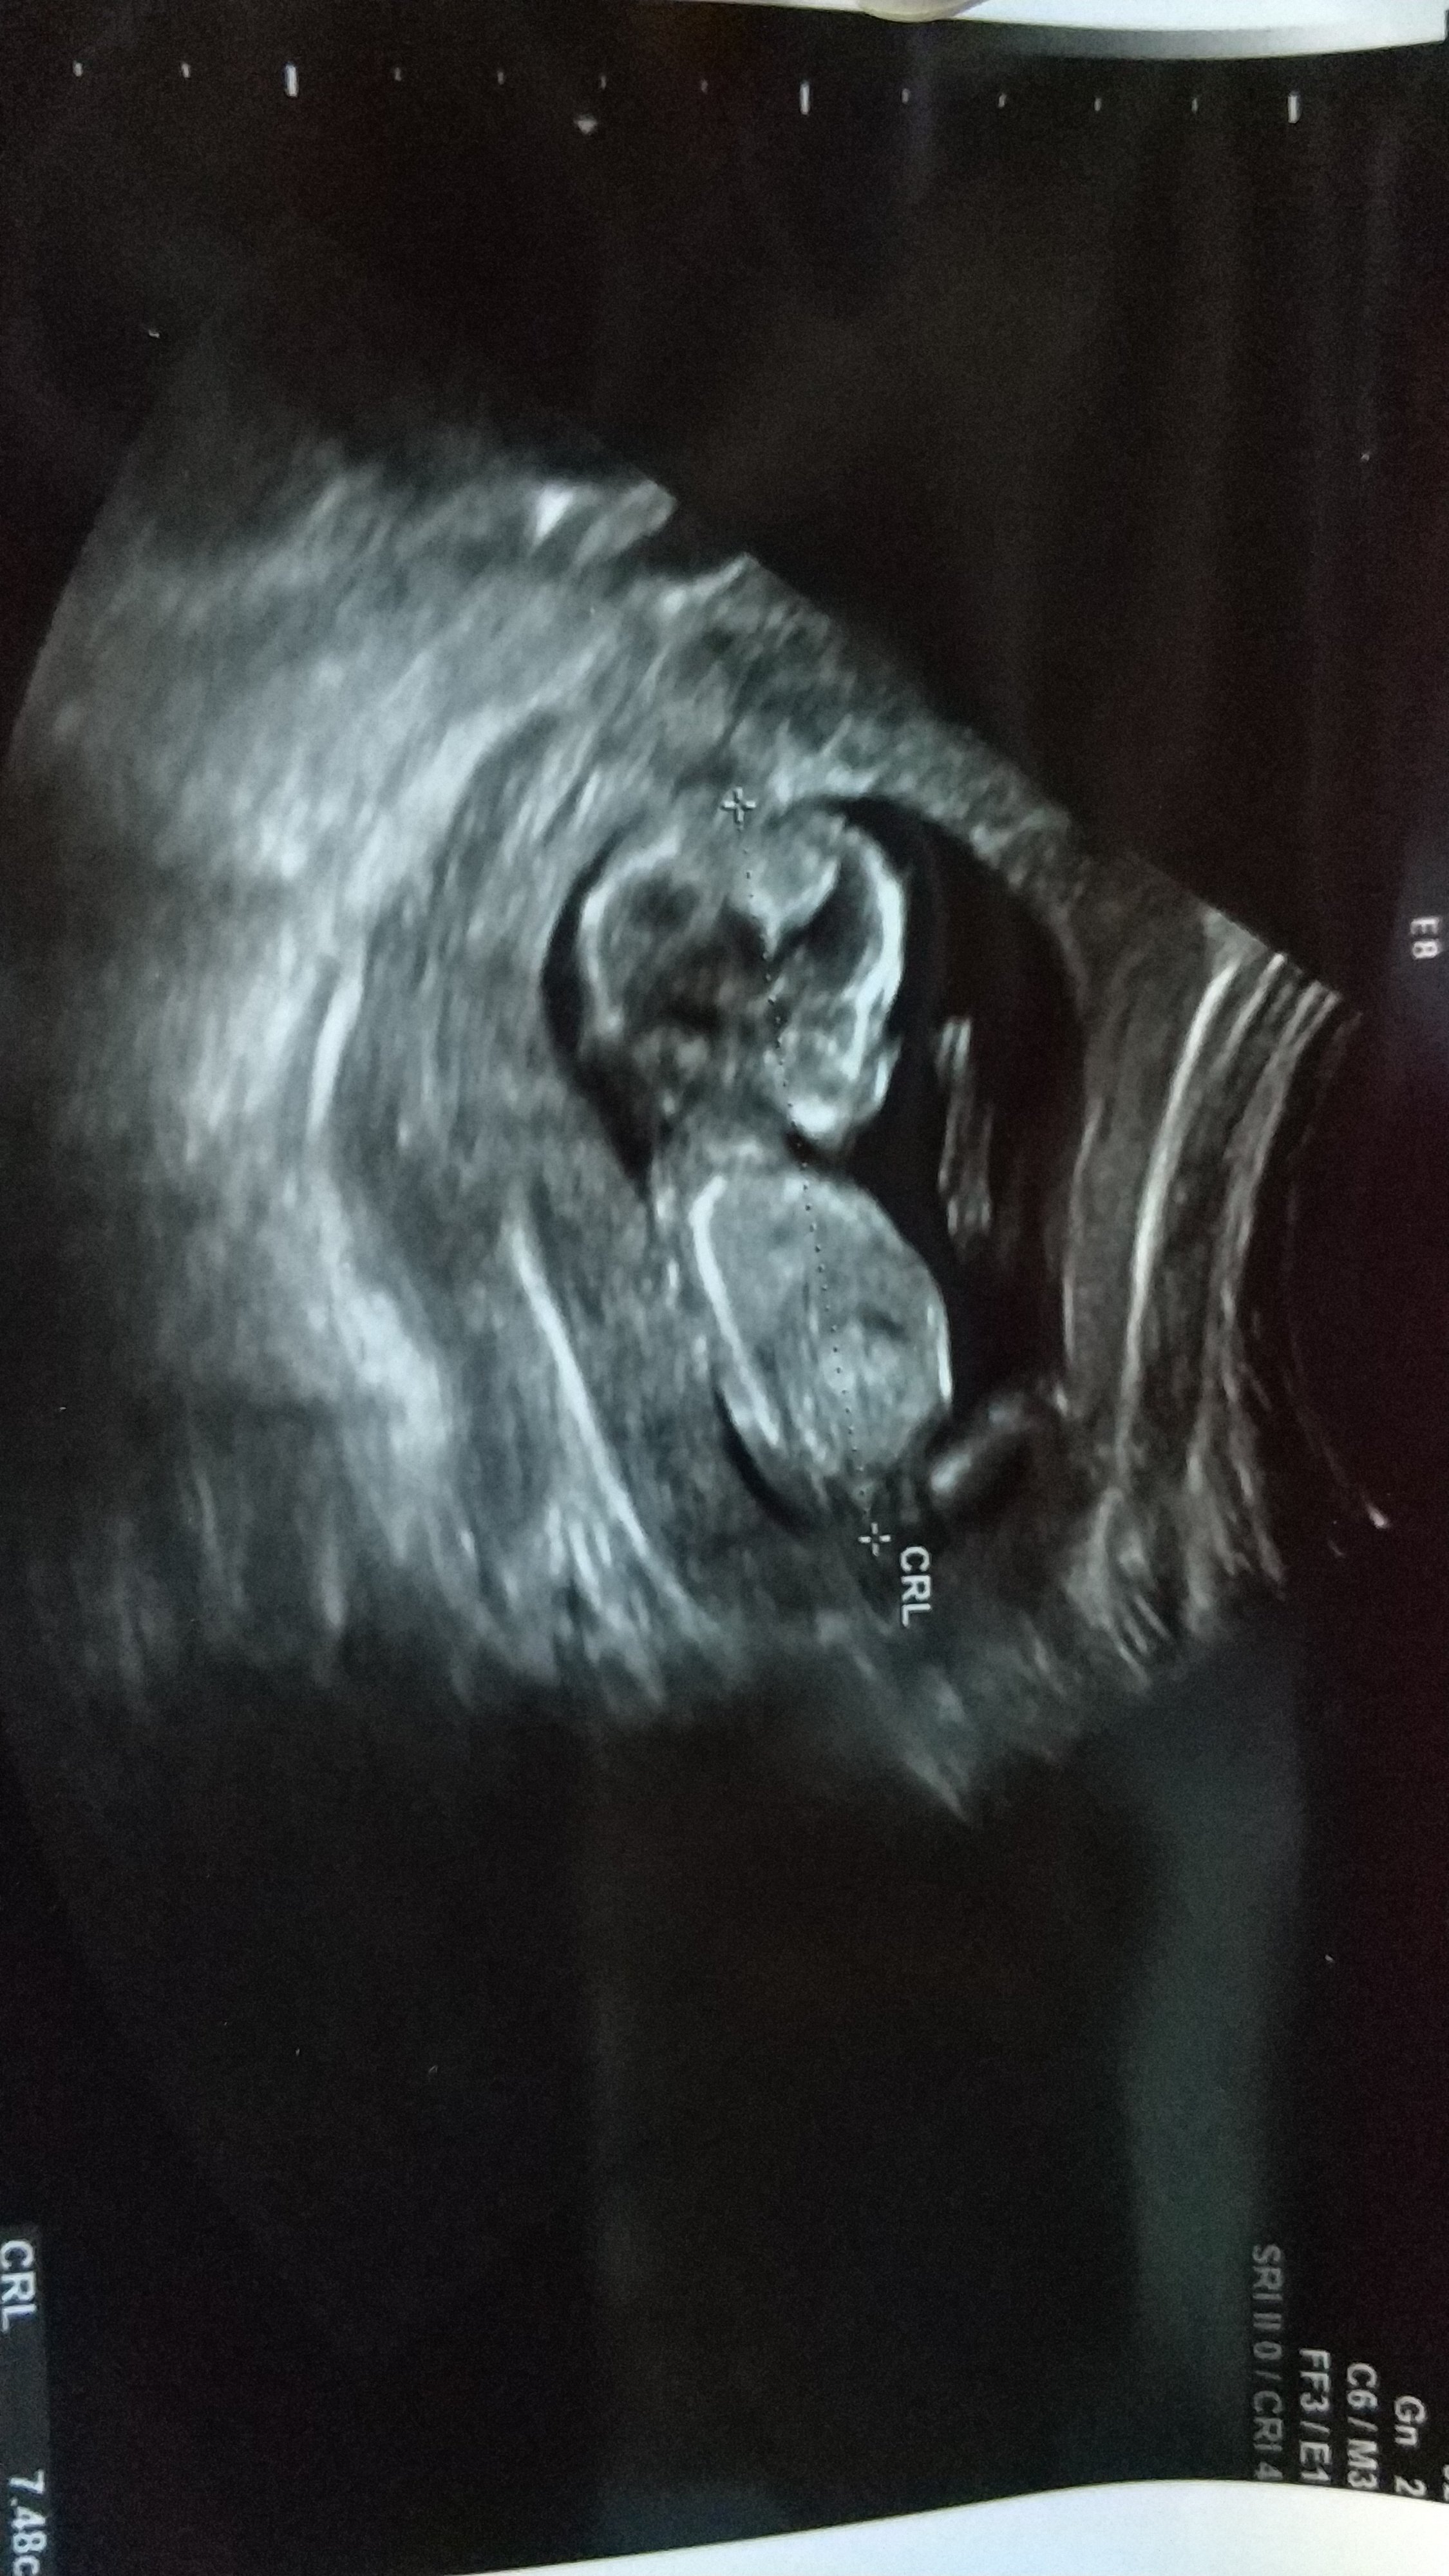

Benim bebeğime de yorum yapabilir misiniz

Rica ederim arkadaşım Allah hayırlısını nasip etsin inşallah .Bebeğinizi sağlıkla kucağınıza almayı diliyorum.Bu arada bebeğinizin cinsiyetini öğrenirseniz mutlaka bizimle paylaşın . Bizlerde hekimler gibi yanılabiliriz. Net olarak 19-20. haftada bebeğinizin cinsiyetini öğrenirsiniz.